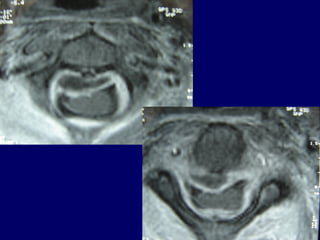

MRIMRI